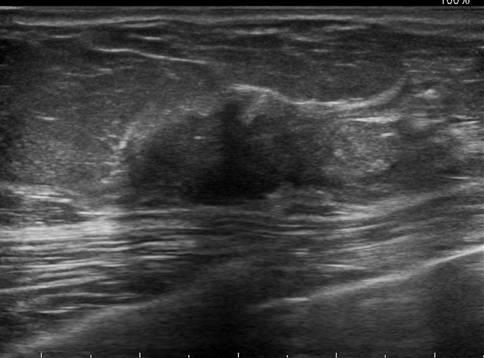

Ung thư vú

» Thông tin: Nữ giới – 76 tuổi.

» Lâm sàng: Khối tuyến vú.